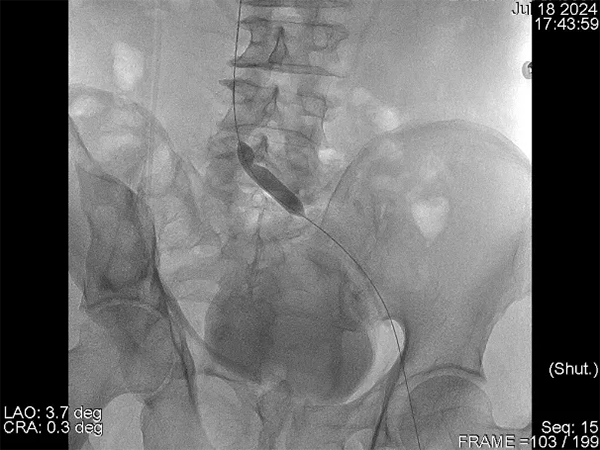

在與患者及家屬進(jìn)行了詳細(xì)的交流后,患者決定住院治療。在經(jīng)過了詳細(xì)的病情分析后,介入科肖晉昌團(tuán)隊(duì)為其制定了“髂靜脈造影+球囊擴(kuò)張+支架置入”的治療計(jì)劃。術(shù)中造影發(fā)現(xiàn)患者左髂總靜脈近心端重度狹窄,周圍側(cè)支開放,狹窄兩端壓差明顯,均提示患者存在重度的髂靜脈壓迫(圖3)。予以球囊擴(kuò)張狹窄處(圖4),然后行支架置入(圖5)。支架置入后造影患者左髂靜脈血液回流明顯改善,周圍側(cè)支減少。術(shù)后由張科醫(yī)師負(fù)責(zé)對(duì)其隨訪,經(jīng)過1個(gè)月的隨訪,患者目前下肢潰瘍基本愈合(圖6)。

圖4 球囊擴(kuò)張